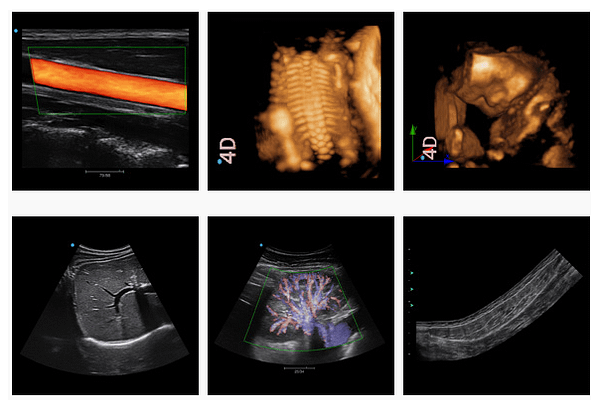

IMT: Tự động xác định độ dày và đo độ dày, cải thiện hiệu quả, độ chính xác và khả năng lặp lại của quá trình kiểm tra.

4D Pro (Có sẵn) Công cụ hình ảnh 4D mới, cho hình ảnh sống động như thật và sự tin cậy trong chẩn đoán.

Opti-4D: Một công cụ tối ưu hóa 4D nhanh giúp để có được một hình ảnh 4D lý tưởng.

nSlice: Hiển thị đa phần của các hình ảnh 4D từ các góc độ khác nhau bằng cách xoay để tìm các hình ảnh cần thiết một cách nhanh chóng. Chẩn đoán chính xác được cải thiện bằng cách điều chỉnh độ dày và góc của hình ảnh này, để quan sát hình dạng, kích thước và môi trường xung quanh của khu vực quét rõ ràng hơn.

Công nghệ Elastography dành cho khám vú: (Có sẵn) Hệ thống hỗ trợ các đầu dò tuyến tính với hình ảnh elastography để hình dung độ cứng của mô trong thời gian thực qua chế độ Mode B / chế độ toàn cảnh. Với công nghệ Elastography được phát triển bởi SIUI, các bác sĩ có thể cảm thấy thuyết phục hơn trong việc phát hiện sớm ung thư vú.

Panoscope (Có sẵn): Mở tầm quét rộng hơn cho các bác sĩ để quét mô diện tích lớn, các hình ảnh toàn cảnh độc quyền Live cũng cho phép các bác sĩ theo dõi chất lượng quét qua màn hình hiển thị đồng thời của chế độ mode B / chế độ toàn cảnh. Ngoài ra, khi hoạt động chức năng này, các bác sĩ có thể xóa các khu vực hình ảnh trước đó và tiếp tục tạo ra hình ảnh toàn cảnh chất lượng hơn.